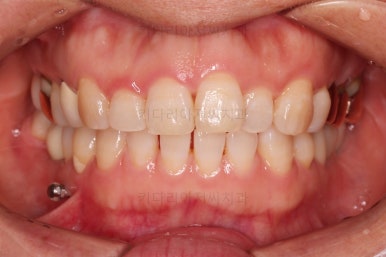

최종 사진을 보여드리겠습니다.

깔끔하게 마무리가 되었네요.

전후 비교입니다.

환자분도 치료에 만족하시어 미적으로 보기싫은 다른 금니들도 하나씩 교체하고 계신 중입니다.

이상 미니스크류를 이용하여 쓰러진 어금니를 연산동부분교정하고, 임플란트를 식립한 치료사례였습니다.